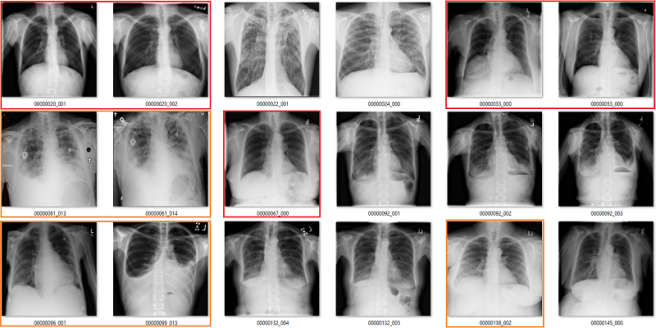

What follows is a bunch of pictures based on the labels in the dataset. In this case, they are pseudo-random. Like I said, it doesn’t have to be perfect. They are randomly chosen sequential sets of 18 images. They are not cherry-picked.

Also, I have tried to err on the side of caution, in the sense that I favour the label class when a case is equivocal.

In all the images, red = clearly wrong label. Orange = I doubt it, I wouldn’t report it, but I can’t really exclude it. Correlate clinically :p

Cardiomegaly

My labels aren’t perfect. Other radiologists will disagree with some of them, and the reduced resolution doesn’t help. But it should be clear that my labels and the results presented in the paper/supplement are vastly different.

I always like hard numbers, so I did my best to quantify the label accuracy where I can. I actually found it very hard to define many of the labels, which is why they are not listed below. I reviewed ~130 images in each class, and calculated the accuracy of the original labels according to my visual interpretation. This is a pretty good amount of data to use, as the 95% confidence intervals will probably be less than +/- 5%, even allowing myself up to a 20% error rate.

Visual analysis by me. Text mining results from the paper.

Again, I doubt my labels are “right” compared to some form of fairly reliable ground truth (like a panel of chest radiologists), but the difference here is stark. I think that these findings make a strong case that these labels do not appear to visually match the diseases they should represent.